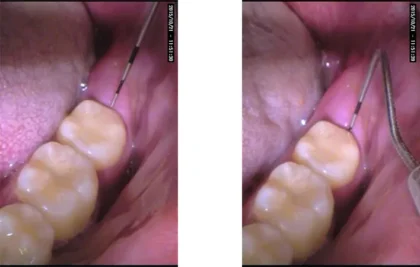

奥に親知らずがあるために部分的に歯周ポケットが深くなっています。

この場合は抜くことをお勧めしています。

親知らずは横に傾いたり、埋まったまま出てこない場合が多く、手前の歯までむし歯になったり、歯ぐきが腫れたりしてトラブルの原因になってしまいます。親知らずはまっすぐ生えている場合には通常の抜歯で対応できますが、横向きに生えていたり、歯ぐきや骨に埋まっていたりする場合は、歯科口腔外科での処置が必要になります。当院ではCTを活用した精密な診断により、神経や血管の位置を把握したうえで、必要に応じて大学病院などの高度医療機関と連携しながら、安全性に配慮した抜歯を行います。

荻窪ツイン歯科・矯正歯科では、CTスキャンを用いて神経や血管の位置をしっかり確認したうえで、できるだけ痛みを抑えた処置を心がけています。症例によっては、大学病院などの専門機関をご紹介することも可能です。